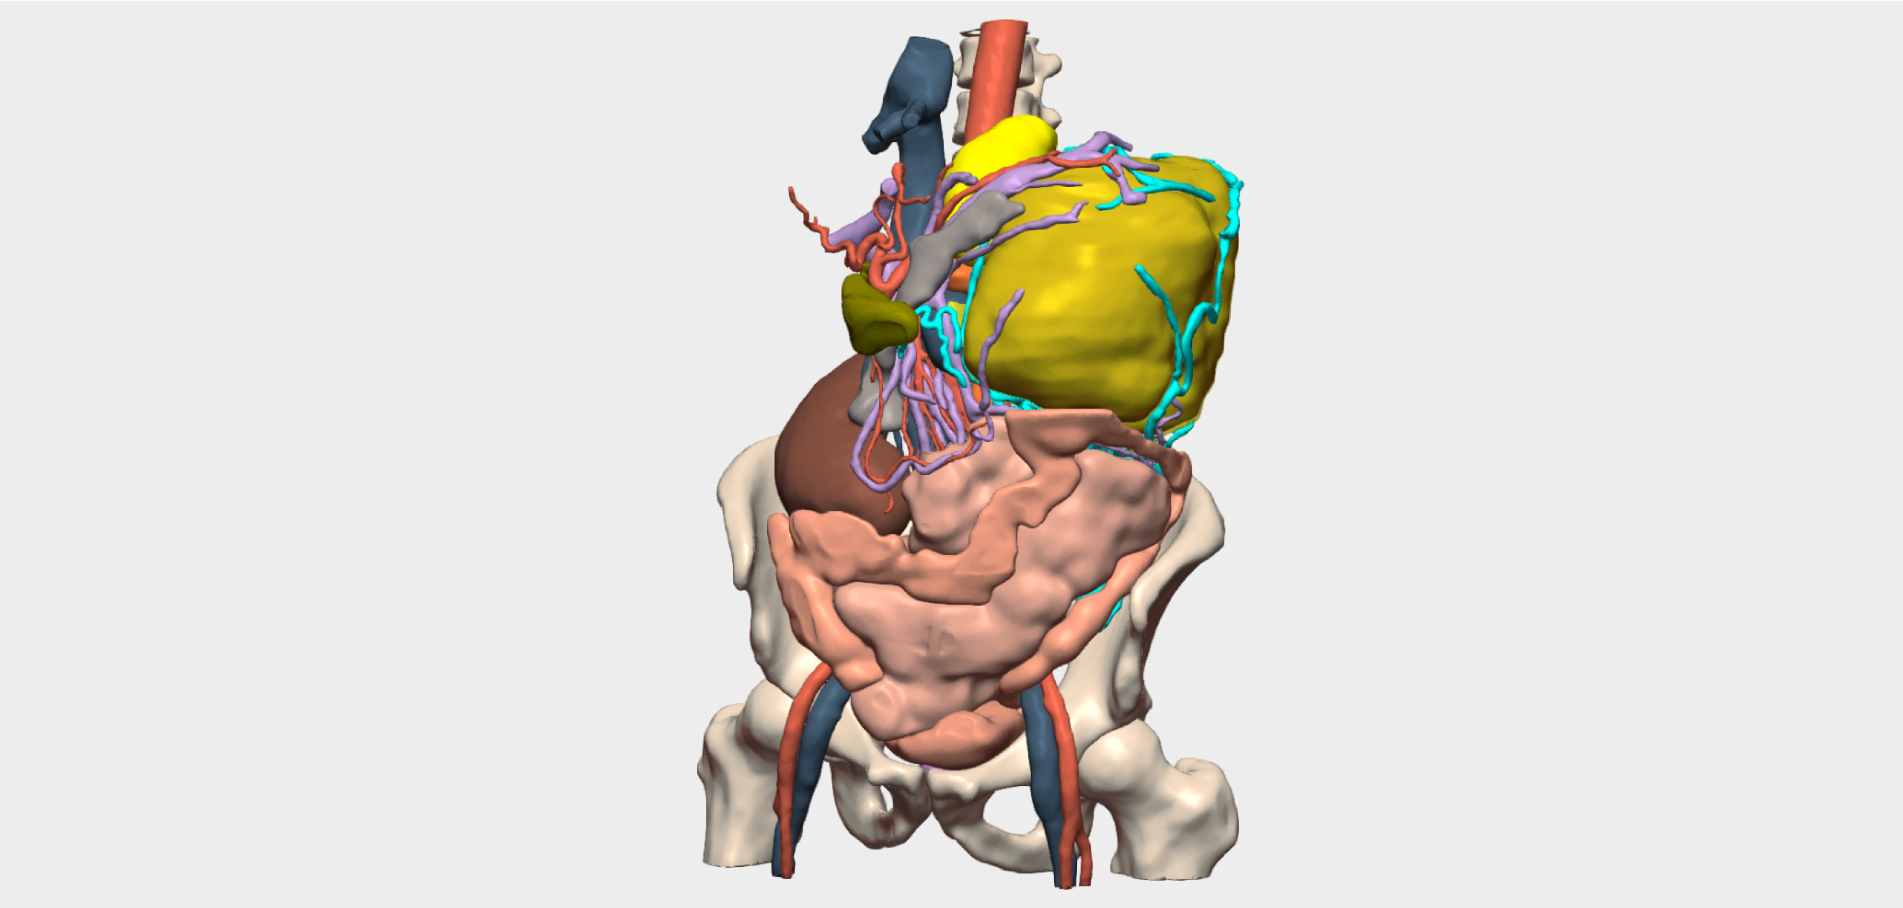

A 12-month-old female patient, weighing 9 kg, was followed by the Paediatric Oncology Service at the Complejo Hospitalario Universitario de Albacete due to a right renal duplication associated with a complex, multilobulated cystic tumour located in the upper renal moiety. The lesion was suggestive of a cystic nephroma and demonstrated progressive growth on follow-up ultrasound, reaching an approximate size of 3 × 3 × 2 cm at the time of surgical evaluation.

Following multidisciplinary assessment by the Oncology Committee, a right upper pole laparoscopic heminephrectomy was indicated for diagnostic histopathological analysis. Imaging studies were inconclusive and did not allow definitive diagnosis or exclusion of malignancy. Additional imaging performed at the Complejo Hospitalario Universitario de Albacete, including MRI and angio-CT, anticipated significant challenges in vascular localisation and dissection. The renal artery and vein bifurcated within the kidney, beneath the tumour and in close contact with it. Furthermore, the small calibre of these vessels limited precise visualisation of their anatomical course.

Given the rarity of the case and the anatomical complexity, the use of a patient-specific 3D model based on the most recent imaging studies was considered essential.

Three-dimensional reconstruction enabled precise localisation of the vascular bifurcation, revealing the presence of two arteries and two veins supplying each renal moiety —an anatomically relevant finding that had not been previously identified and was critical for surgical planning.

Detailed 3D anatomical analysis, combined with advanced functionalities such as arterial territory assessment and the ability to work intraoperatively with dual visualisation —3D reconstruction and laparoscopy displayed simultaneously— was a key factor in the success of the procedure.